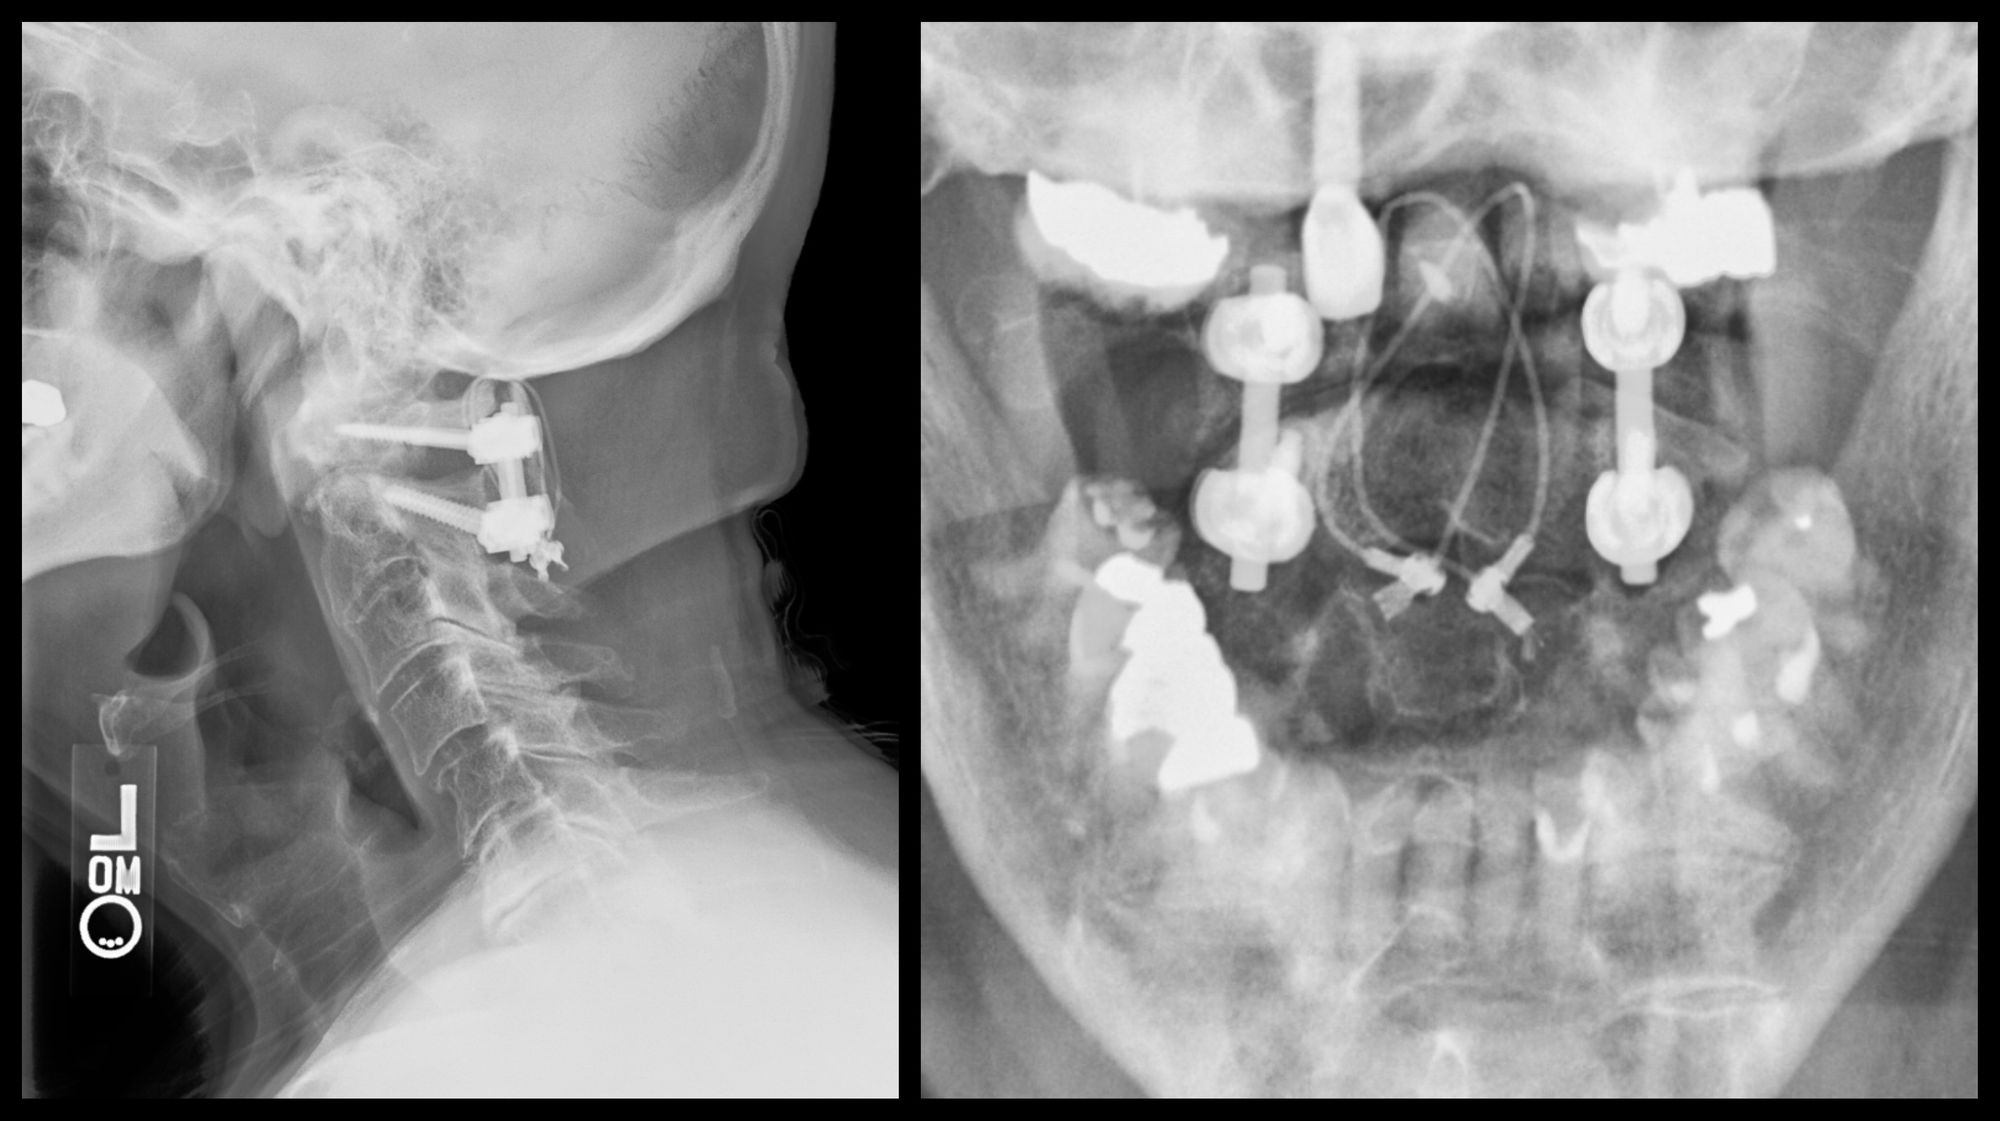

C1-2 Fusion